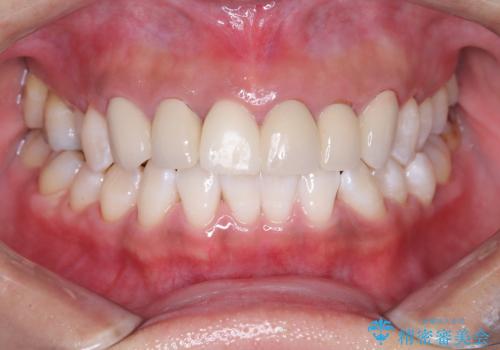

ステインがたくさん付着していたので、エアフローを用いてステインを除去しました。そのため、直後の写真は歯肉からの出血が見られます。

まず歯石取りを行い歯肉の状態を改善後、後日PMTC30分コースをしました。